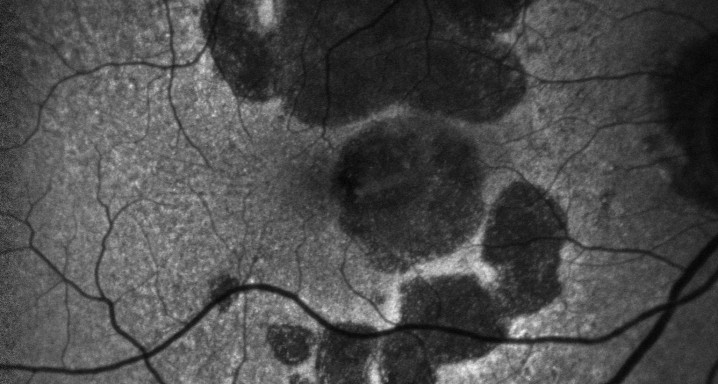

Patients were evaluated with the use of imaging techniques that included 35° fundus photography, infrared, fundus autofluorescence (FAF), and SD-OCT. Visualization of the fundus with FAF was done simultaneously with OCT. Two acquisition protocols were followed: a macular cube for coverage (19 horizontal B-scans centered on the fovea) and high-resolution horizontal B-scan for qualitative foveal detail.

A marked hyporeflective wedge-shaped structure, with its base on Bruch's membrane and its apex pointing toward the inner limit of the outer plexiform layer (OPL) adjacent to the margin between the atrophied area and the preserved retina, was observed in 72.9% of eyes (70/96; 95% confidence interval, 63.9-82.0). This hyporeflective band appeared to be within the OPL. Using eccentric SD-OCT acquisition, the boundaries between the outer nuclear layer (ONL) and Henle's fiber layer (HFL) were well defined, showing that the ONL ends before the margin of atrophy of the retinal pigment epithelium (RPE). A narrow hyperreflective band separated the margin of the ONL and RPE from the hyporeflective band, already within the atrophic area.

A hyporeflective wedge-shaped structure appears frequently within the boundaries of the OPL in patients with GA secondary to AMD, corresponding to an increase in the width of the HFL, presumably because of axonal swelling or interaxonal edema. This finding may improve the interpretation of SD-OCT images of the outer layers, may help in understanding better the interactions between photoreceptor cells and the RPE, and may help in the development of monitoring techniques and therapies for GA secondary to AMD.